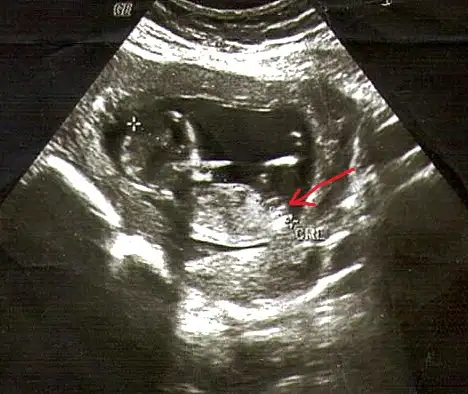

Eki Görüntüle 473829 bu bir erkek bebek genital nub cikintisi gayet yukarda

Eki Görüntüle 473831 simdi burada cikintilara bakin eger bel popo cizgisine paralel ise kiz

yok 30 derecelik bir aciyla yukari bakiyorsa erkek